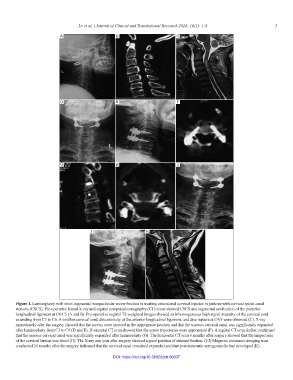

Figure 1. Laminoplasty with short-segmental transpedicular screw fixation in treating extensional cervical injuries in patients with cervical spinal canal

stenosis (CSCS). Pre-operative lateral X-ray and sagittal computed tomography (CT) scans showed CSCS and segmental ossification of the posterior

longitudinal ligament at C4-C5 (A and B). Pre-operative sagittal T2-weighted images showed an inhomogeneous high signal intensity of the cervical cord

extending from C3 to C6. A swollen cervical cord, discontinuity of the anterior longitudinal ligament, and disc rupture at C4/5 were observed (C). X-ray

immediately after the surgery showed that the screws were inserted in the appropriate position and that the osseous cervical canal was significantly expanded

after laminoplasty from C3 to C6 (D and E). Horizontal CT scan showed that the screw trajectories were appropriate (F). A sagittal CT scan further confirmed

that the osseous cervical canal was significantly expanded after laminoplasty (G). The horizontal CT scan 6 months after surgery showed that the hinged side

of the cervical lamina was fused (H). The X-ray one year after surgery showed a good position of internal fixation. (I-J) Magnetic resonance imaging scan

conducted 24 months after the surgery indicated that the cervical canal remained expanded and that post-traumatic syringomyelia had developed (K).